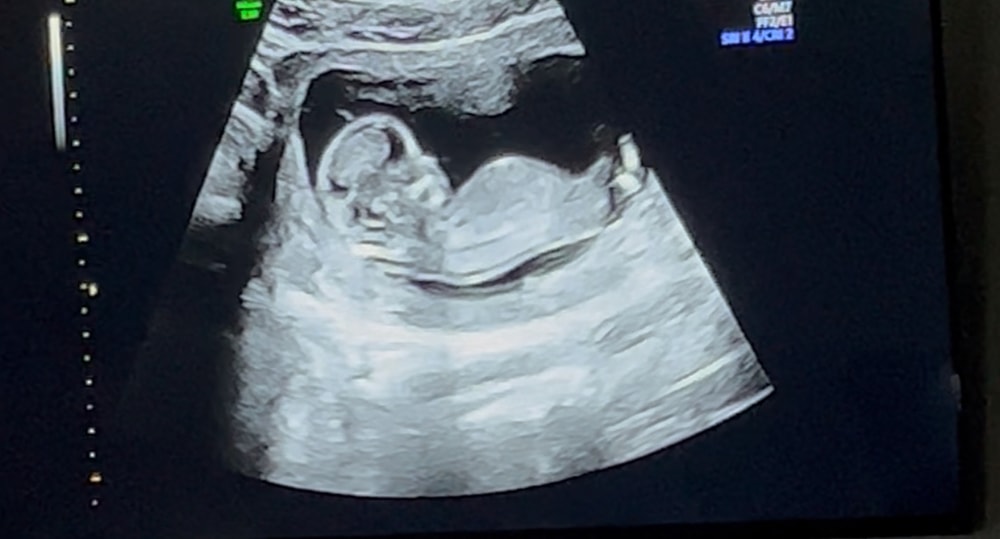

Валерия в Благополучная беременность 4 месяца Пол ребенка Анализы, скрининги Девочки, можно ли как-то по таким снимкам предположить пол ребенка? Посмотрите еще 20 записей на эту тему Отменить Ответить Карамелечка Похоже на мальчика🙂 08.08.2025 Ответить Tatiana А я за девочку ☺️ 07.08.2025 Ответить Анастасия Думаю, что мальчик) Но это скорее гадание) 07.08.2025 Ответить GinBerry Можно, погуглите про половой бугорок. Похоже, что это он у вас на втором фото 07.08.2025 Ответить Преждевременное старение плаценты Локб Скрининг Чаты Беременных Выберите чат: Январята-2026 Февралята-2026 Мартята-2026 Апрелята-2026 Майчата-2026 Июнята-2026 Июлята-2026 Августята-2026